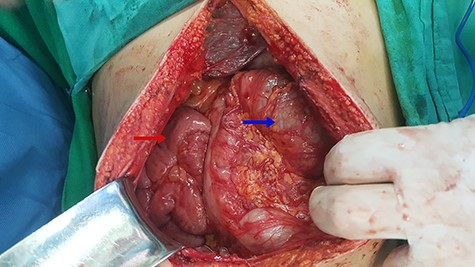

Laparoscopic surgery was excluded for technical and anatomical difficulties; we switched to open surgery. During intraoperative, we found malrotation (90° counterclockwise), where the small intestine was on the right side and the colons were on the left side (Fig. 2), and small intestine was slightly dilated and entrapped within a congenital hernia in the mesentery of the transverse colon (Fig. 3).

Red arrow indicates to the small intestine and blue arrow indicates to the colons.

Small intestinal entrapped within a congenital transmesocolic hernia.